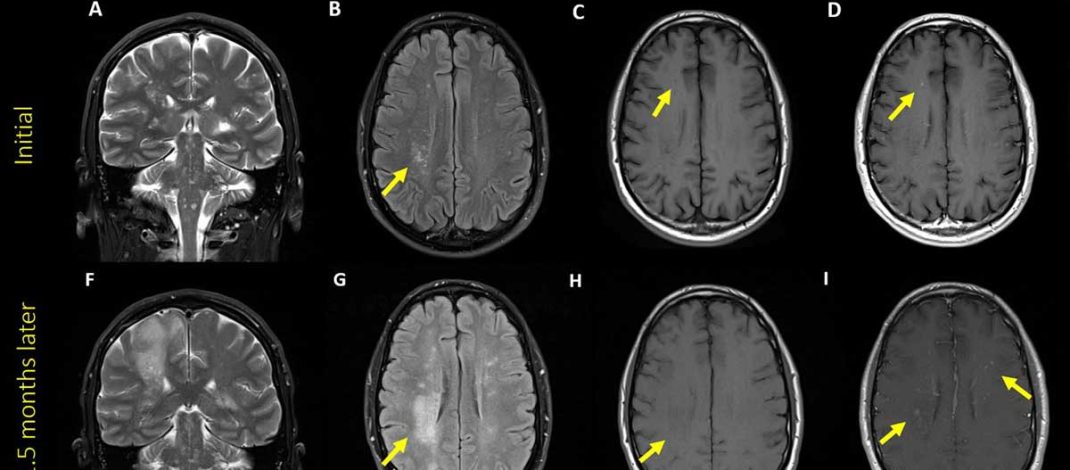

Longitudinal Changes in Cognition and Brain Imaging in Persons with HIV

James Kennedy, Sarah A Cooley, June Roman Fox, Kalen J Petersen, Elizabeth Westerhaus, Pat Reid, Linet Lopez, Beau M Ances Abstrak Latar Belakang: Seiring